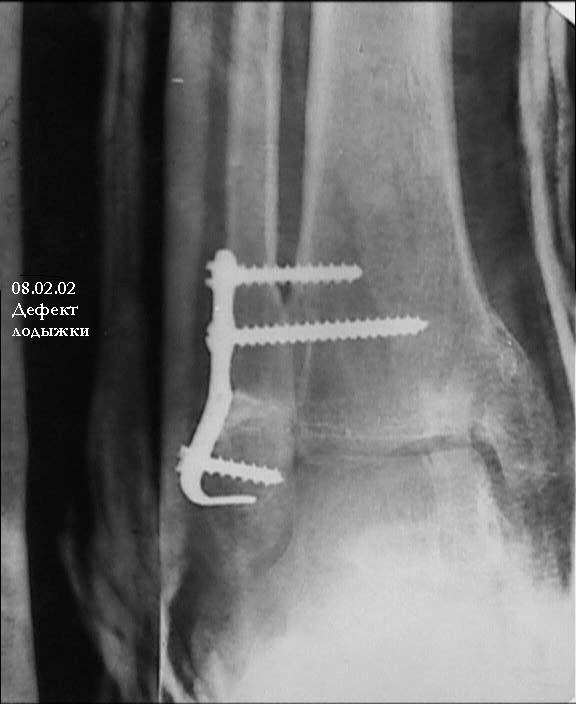

Провели костную аутопластику дефекта, металлоостеосинтез наружной лодыжки Г-образной пластиной и 4 винтами. Снимок 1, Снимок 2.

При проведении винтов выше перелома выявлен остеопороз. Есть опасность, что винты не удержат пластину при ранних нагрузках, поэтому провели винты через межберцовый синдесмоз.

Большинством мнений врачей в нашем отделении решено не проводить вмешательства на внутренней лодыжке.

Решено проводить иммобилизацию гипсовой лонгетной повязкой только в ближайшем послеоперационном периоде, разрешить ограниченную нагрузку весом тела (2 нед.). В последующем будем рекомендовать увеличивать нагрузку, проводить разработку в суставе.